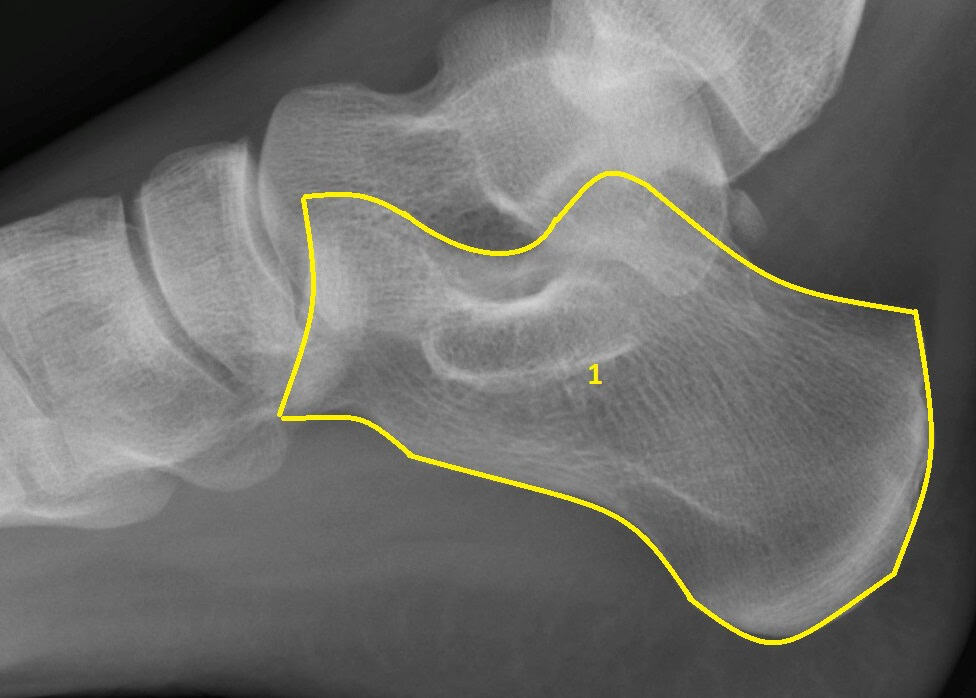

Unlike an adult heel bone the heel bone in a child is in two parts connect by a cartilage growth plate (see picture below).

Xray of a Child's Foot